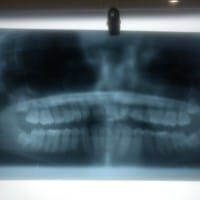

Tengo los segundo molares doblados, tengo que sacarme las muelas del juicio?